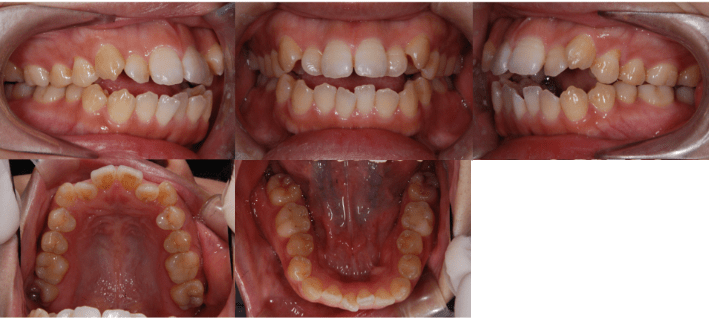

治療前

• 初診時年齢:28歳4ヶ月

• 主訴:前歯のかみ合わせ

• 診断:開咬

• 抜歯箇所:上下左右4

• 治療内容:小臼歯4本を抜歯した後に、マウスピース型カスタムメイド矯正歯科装置(製品名インビザライン 完成物薬機法対象外)を使用して主訴である開咬の改善を行いました。

• 治療期間:2年

• リスク:矯正治療による歯の移動に伴う痛み、歯根吸収、虫歯

• 費用:80万円